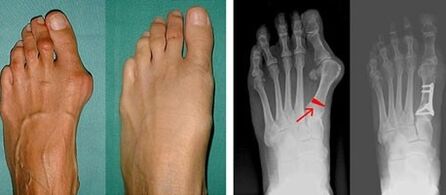

In the first stage of identification of big toe and little toe valgus, the doctor performs a visual examination.In this way, it determines the stage of development of the pathology.In order to identify detailed changes in the joints, X-rays and plantography are prescribed.

If visual inspection and x-rays are inconclusive, the patient is referred for plantography to determine possible flat feet.This method includes the impression of the foot, on the basis of which shoes or insoles with orthopedic properties are made for the patient.The patient is then prescribed podometry.This method uses computer analysis to determine the pressure of a person's weight on the foot.The results of the advanced diagnostics are the basis for choosing the treatment method for the curvature of the first and second toes.

The disadvantage of X-ray examination is that the patient's leg has to be irradiated, which many patients do not like.They think this method is too harmful.In this regard, effective treatment of hallux valgus cannot be started without the results of plantography.